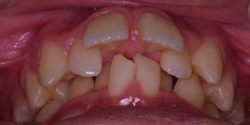

↓歯列(下顎)が左へズレている例(初診時)

.⇒.

.:矯正治療中

☆上下のアーチの形をライトワイヤー装置にて

修正すると,下顎のズレが解消されました.